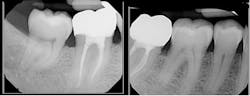

I have been a dental hygienist for almost 25 years, and I am proud to say I do not practice dental hygiene in the exact manner I was taught in school. Over my career I learned on the job how to incorporate many new advancements such as digital x-rays, lasers, air polishing, contemporary ultrasonic instrumentation, digital scanning, and AI technology.

Dental hygiene is a fascinating field that has done nothing but grow and improve patient experiences and outcomes over time. One of the more recent technology changes involves debridement techniques. The arrival of air polishing devices that have multiple therapeutic and preventive applications have changed the landscape of dental hygiene procedures.